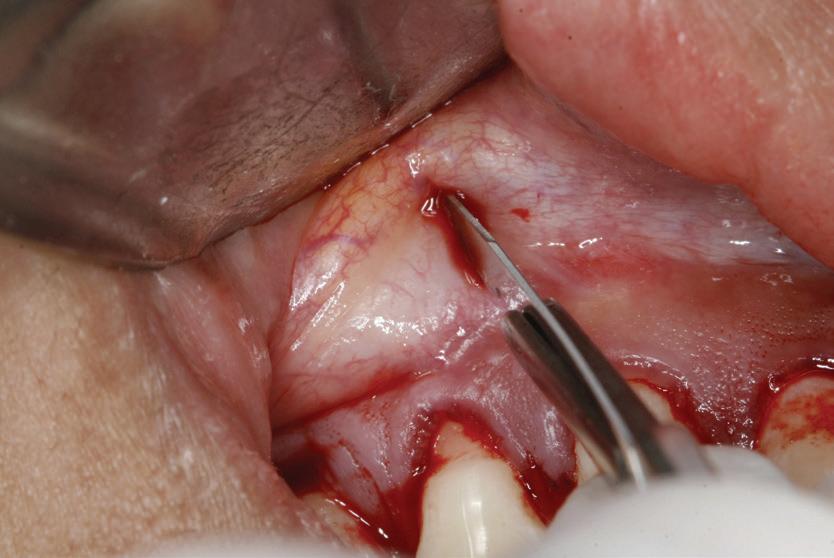

Lamboul repoziționat apical

Această tehnică este o opțiune atunci când nu există suficient țesut gingival keratinizat și este preferată atunci când caninul impactat este situat mezial față de incisivul lateral. Lamboul trebuie fixat și adaptat la dinte. Dezavantajele includ riscul de recesie și marginea gingivală neregulată, alături de necesitatea unei intervenții chirurgicale osoase extinse. Se efectuează incizii verticale, iar lamboul este deplasat într-o direcție laterală sau apicală. Se recomandă un design al lamboului în care baza și zona coronară sunt fie la aceeași lățime, fie mai înguste la bază, cu o grosime de 4-5 mm, astfel încât lamboul să fie suficient de lat meziodistal, extinzându-se cu 1,5 mm dincolo de unghiul dintelui (fig. 6, 7).

Osul acoperitor trebuie îndepărtat cu chiuretă sau freză diamantată pentru a expune porțiunea liberă a coroanei. Lamboul se poziționează apoi la CEJ și se fixează cu suturi periostale pentru o stabilitate mai mare. În funcție de gradul de impactare a caninului, se poate plasa un pansament parodontal, astfel încât țesutul să nu se închidă. Bracketul este plasat fie în momentul procedurii, fie la 10 zile postoperator. Dacă respectivul canin este situat prea apical, se preferă tehnica închi-

să. În general, deplasarea ortodontică începe la 4-6 săptămâni după expunerea chirurgicală. Când foliculul ce înconjoară caninul este larg, incizia lamboului trebuie făcută peste limitele acestuia, pentru a permite adaptarea optimă a lamboului la coroană și os. Pentru a determina buna adaptare a lamboului, atunci când buza se mobilizează, acesta ar trebui să rămână staționar.

6, 7. Utilizarea lamboului repoziționat apical pentru a gestiona caninii bilaterali cu impactare facială. După expunere, s-a practicat și frenectomia și au fost plasate bracketuri bilaterale (fig. 6). S-a realizat tracțiunea ortodontică, ce a permis poziționarea corespunzătoare a ambilor canini pe arcada superioară (fig. 7)

apoi direcționarea vestibulară a caninului (fig. 8, 9).